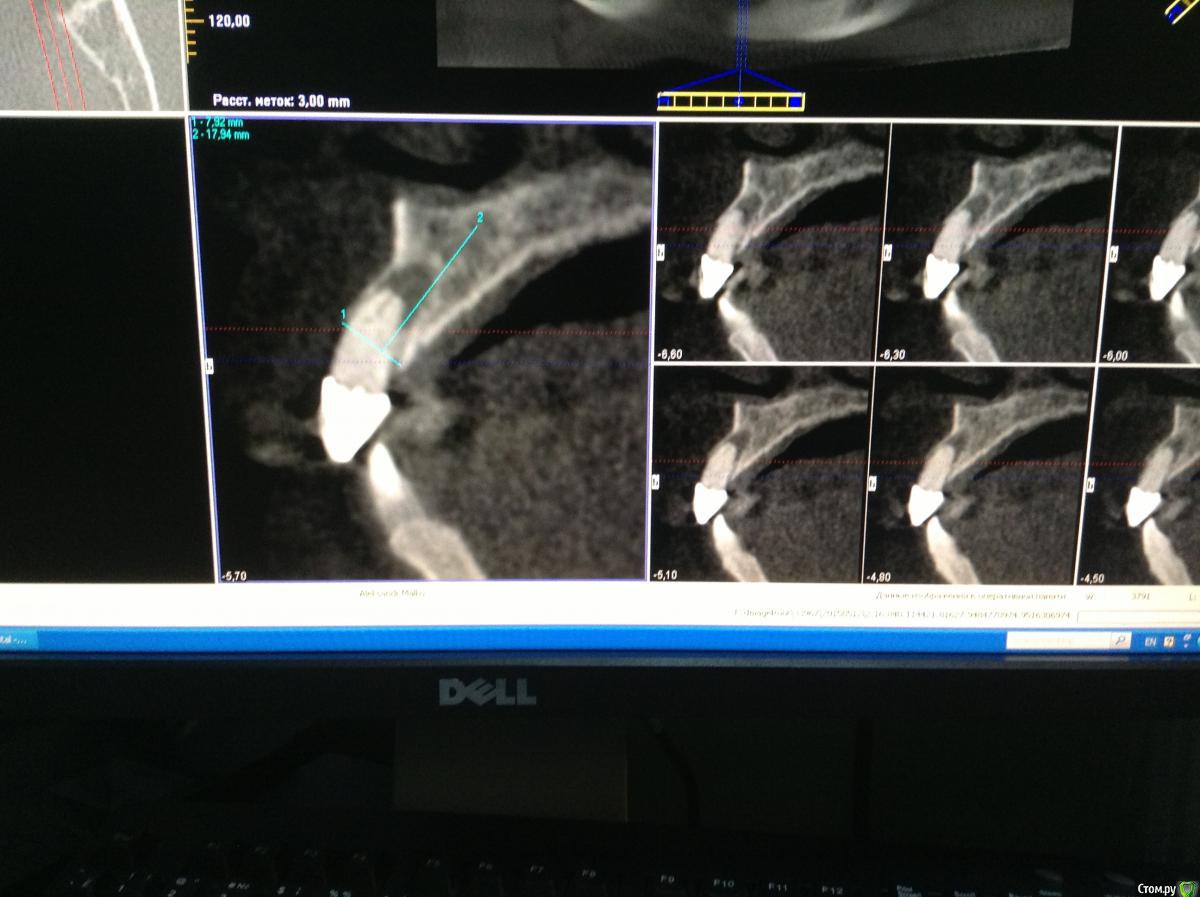

Pro100Andre Опубликовано 5 июня, 2015 Автор Поделиться Опубликовано 5 июня, 2015 12 терапевты усмотрели резорбцию корня говорят не стоит оставлять, если в два этапа не ухудшит ли это прогноз для 11? да еще 12 под медиальным наклоном стоит, если имплантат ставить то ближе к клыку получится думаю стабилизация первичная норм будет Ссылка на комментарий

Romanson Опубликовано 5 июня, 2015 Поделиться Опубликовано 5 июня, 2015 Терапевты углядели резорбцию сказали сохранять не вариантА мост сняли уже? Как там с твердыми тканями 1.2? Если норм, то почему бы не попытаться спасти его? Всё-равно лоскут откидывать будете во время имплантации 1.1, так можно заодно ретроградно пролечить 1.2... А можно и не ретроградно, а просто под кальцием. Если положительной динамики не будет, то уж тогда удалять, а до этого времени он прослужит опорой для временной конструкции, если 1.1 одномоментно нагрузить не получится. А где терапевты резорбцию углядели, стрелочкой показать можете? Ссылка на комментарий

Гарриевич Опубликовано 6 июня, 2015 Поделиться Опубликовано 6 июня, 2015 Разделив на две операции я вижу только минусы.Однозначно оба импланта сразу в день удаления 12.если не трудно, покажите на снимке причины удаления 12хоть убей, не могу углядеть Ссылка на комментарий